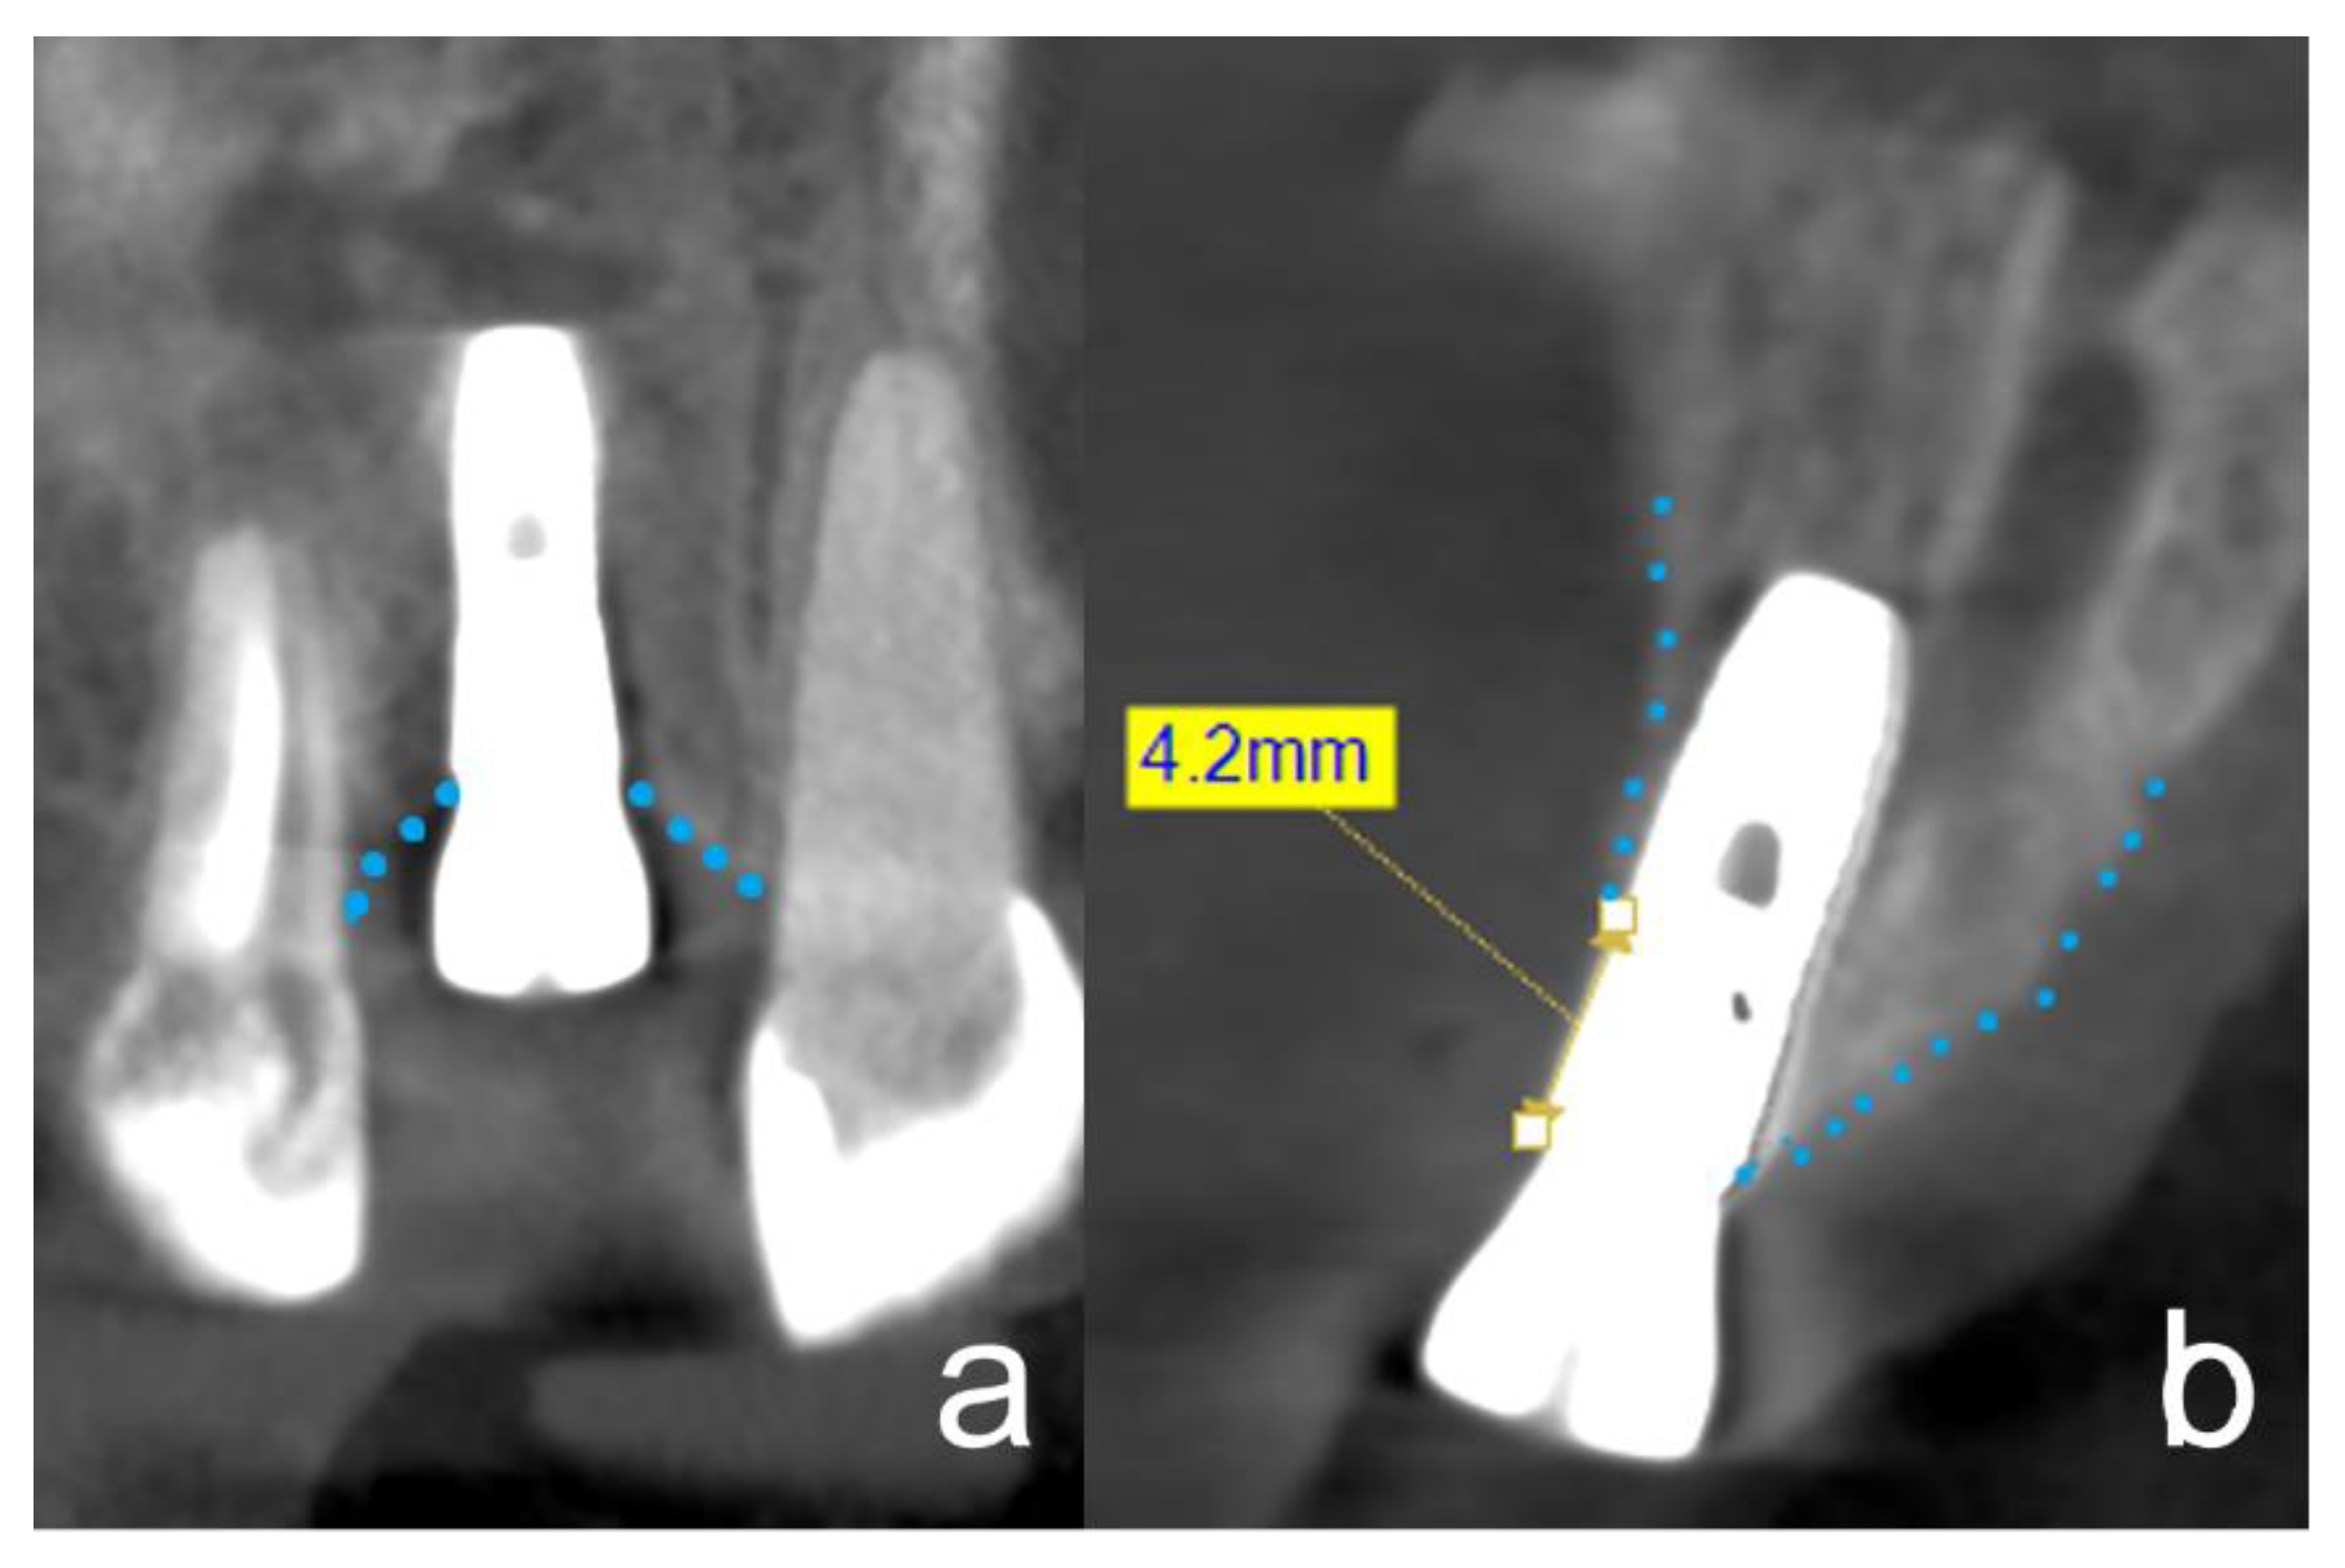

2.3. Clinical Procedure of the Tooth Processing

2.6. Radiographic Evaluation of Bone Gain and Resorption

4.3. Radiographic Evaluation of Bone Gain